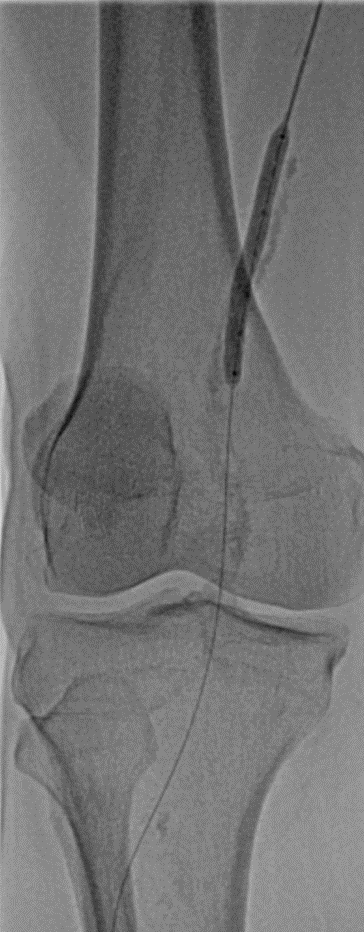

随后使用LiqMagic?P18外周血管内冲击波导管进行钙化斑块的压裂。根据血管尺寸,团队选择了4.0*60mm和5.0*60mm两个规格在4atm压力下逐段扩张整段病变,共进行了6个周期的冲击波治疗,将冲击波球囊加压至12atm显示病变狭窄解除,均匀扩开,保压1min后造影结果显示血流恢复通畅,钙化部位的残余狭窄明显改善。

▲5*60冲击波球囊扩张